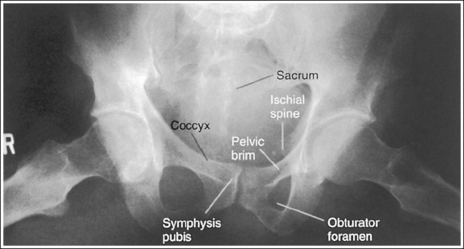

The pelvis demonstrates an AP projection. The ischial spine is aligned with the pelvic brim, the sacrum and coccyx are aligned with the symphysis pubis, and the obturator foramen is open.

• Detecting pelvis rotation. Rotation on an AP hip projection is initially detected by evaluating the relationship of the ischial spine and the pelvic brim, the alignment of the sacrum and coccyx with the symphysis pubis, and the degree of obturator foramen demonstration. If the patient was rotated toward the affected hip, the ischial spine is demonstrated without pelvic brim superimposition, the sacrum and coccyx are not aligned with the symphysis pubis but are rotated away from the affected hip, and the obturator foramen is narrowed (see Image 1). If the patient has been rotated away from the affected hip, the ischial spine is not aligned with the pelvic brim but is demonstrated closer to the acetabulum, the sacrum and coccyx are not aligned with the symphysis pubis, but are rotated toward the affected hip, and the obturator foramen is widened (see Image 2).

The pelvis demonstrates an AP projection. The ischial spines are aligned with the pelvic brim, the sacrum and coccyx are aligned with the symphysis pubis, and the ilia and obturator foramina are open and uniform in size and shape.

• Pelvic rotation. A nonrotated AP pelvis projection demonstrates symmetrical ilia and obturator foramina. Rotation is initially detected by evaluating the relationships of the ischial spines with the pelvic brim and of the sacrum and coccyx with the symphysis pubis. The ischial spines should be aligned with the pelvic brim, and the sacrum and coccyx should be in alignment with the symphysis pubis on a nonrotated pelvis. If the pelvis is rotated into a LPO position, the left ilium is wider than the right, the left obturator foramen is narrower than the right, the left ischial spine is demonstrated without pelvic brim superimposition, and the sacrum and coccyx are not aligned with the symphysis pubis but are rotated toward the right hip (see Image 16).

The sacroiliac joints are demonstrated in an AP axial projection. The median sacral crest is aligned with the symphysis pubis and the sacrum is at an equal distance from the lateral wall of the pelvic brim on both sides.

• Detecting sacroiliac joint rotation. Rotation is detected on an AP axial sacroiliac joint projection by evaluating the alignment of the long axis of the median sacral crest with the symphysis pubis and the distance from the sacrum to the lateral pelvic brim. When the patient is rotated away from the supine position, the sacrum moves in a direction opposite from the movement of the symphysis pubis and is positioned next to the lateral pelvic brim situated farther from the imaging table. If the patient is rotated into an LPO position, the sacrum is rotated toward the patient's right pelvic brim. If the patient is rotated into an RPO position, the sacrum rotates toward the patient's left pelvic brim.